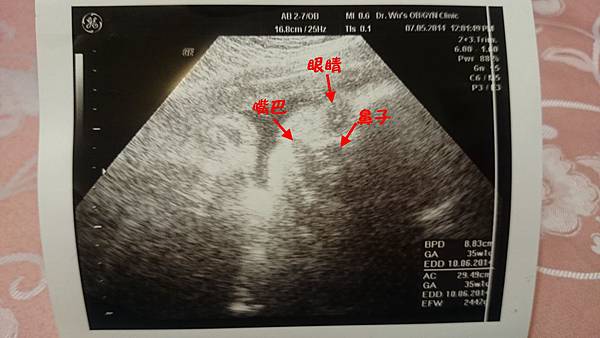

【孕期】終於邁入2000g了